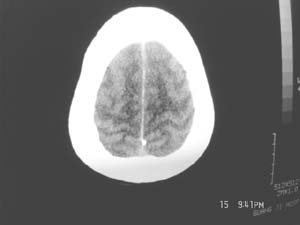

女,60岁,反复头痛3天,呕吐3小时伴昏迷10分钟入院检查。

右额叶占位,有占位效应,中线偏移,病灶位于镰旁,呈囊实性并有钙化,

考虑:1.脑膜瘤。2.胶质瘤。

理由:1.病灶位于前颅凹及镰旁,有明显占位效应---支持脑膜瘤。

2.病灶呈囊实质性并有条状钙化,符合胶质瘤改变;

另外也不排除包虫病的可能。

右额叶占位,有占位效应,中线偏移,病灶位于镰旁,呈囊实性并有钙化 kaolv  少枝胶质瘤。胶质瘤。

病变范围较大,累及左额叶,内见钙化。及高密度灶。考虑;胶母伴卒中可能大。